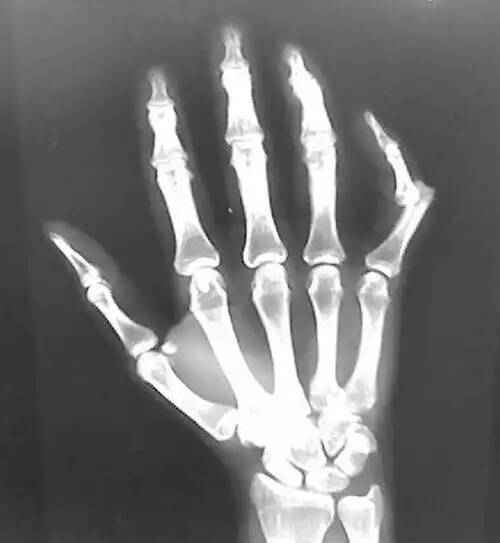

دررفتگی ( به انگلیسی: luxation ) یک جابجایی دائمی در سطوح مفصلی نسبت به یکدیگر است. دررفتگی کامل در صورت از دست دادن ارتباط بین دو سطح مفصلی کامل است ولی هنگامی که قطع تماس مشتقات مفصلی جزئی باشد٬ دررفتگی نسبی ( subluxation ) نام می گیرد. در هنگام دررفتگی کامل٬ مفصل چنان پیچیده یا کشیده شده که استخوان ها از محل طبیعی خود در مفصل خارج یا جابه جا شده و ممکن است رباط ها نیز کشیده یا پاره شوند.

جابه جاشدن استخوان های تشکیل دهندۀ یک مفصل. این جابه جایی باعث درد، تورم، کاهش عملکرد مفصل، و تغییر شکل آن می شود. علت دررفتگی معمولاً تصادف است، ولی ممکن است ناشی از بیماری باشد یا به صورت مادرزادی (دررفتگی قبل از تولد) بروز کند. درمانِ این عارضه برگرداندن استخوان ها به حالت اولیه است که با دستکاری مفصل، تحت بی حسی موضعی یا بیهوشی عمومی، ممکن می شود. دررفتگیِ شانه و آرنج موارد شایع دررفتگی اند. ممکن است ضمن دررفتگی شکستگی نیز واقع شود. دررفتگی ممکن است کامل یا جزیی باشد. اگر در محل دررفتگی پوست سالم باشد، دررفتگی ساده، و اگر استخوانِ جابه جا شده باعثِ پارگی پوست شود، دررفتگی مرکب نامیده می شود. دررفتگیِ عارضه دار جابه جایی استخوان با آسیب دیدگی شدید بافت های نرم اطراف یا شکستگی استخوان است. عمل اصلاح دررفتگی جا انداختن نامیده می شود. در مواردِ دررفتگی مادرزادی سر استخوان ران، در یک یا هر دو پا، این استخوان نسبت به استخوان لگن در وضعیت طبیعی قرار ندارد. علت این عارضه آسیب دیدگی نیست، بلکه علت رشد نابجای استخوانی است. این حالت در دخترها شایع تر است و کمی پس از تولد با احساس «تق» در مفصل مبتلا تشخیص داده می شود. برای درمان باید پا به حالتی قرار گیرد که سر استخوان ران در محل مناسب، روی استخوان لگن، ثابت شود. این امر گاه با گچ گرفتن صورت می گیرد. گاه دررفتگی مادرزادیِ مفصل بالای ران تا زمان راه افتادن کودک تشخیص داده نمی شود. در این صورت، مشکل دررفتگی به صورت لنگیدن یا راه رفتن اردکی آشکار می شود. ممکن است اصلاح دررفتگی در این حالت نیاز به جراحی داشته باشد. درمان نکردن این نوع دررفتگی باعث بروز استئوآرتریت (آرتروز) شدید در مفصل بالای ران می شود.